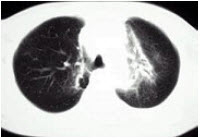

3、单项选择题

患者输液过程中突发胸闷,气急,咳痰,胸部正侧位片如图,最可能的诊断为()

A.硅沉着病合并感染

B.中央型肺水肿

C.真菌感染

D.间质性肺水肿

E.腺病毒肺炎